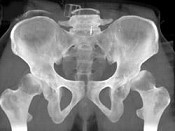

男,23岁,跛行,外展受限,两下肢不等长,结合图像,最可能的诊断是()

• A.髋关节中心脱位

• B.髋关节后脱位

• C.髋关节前脱位

• D.先天性髋内翻

• E.髋关节结核